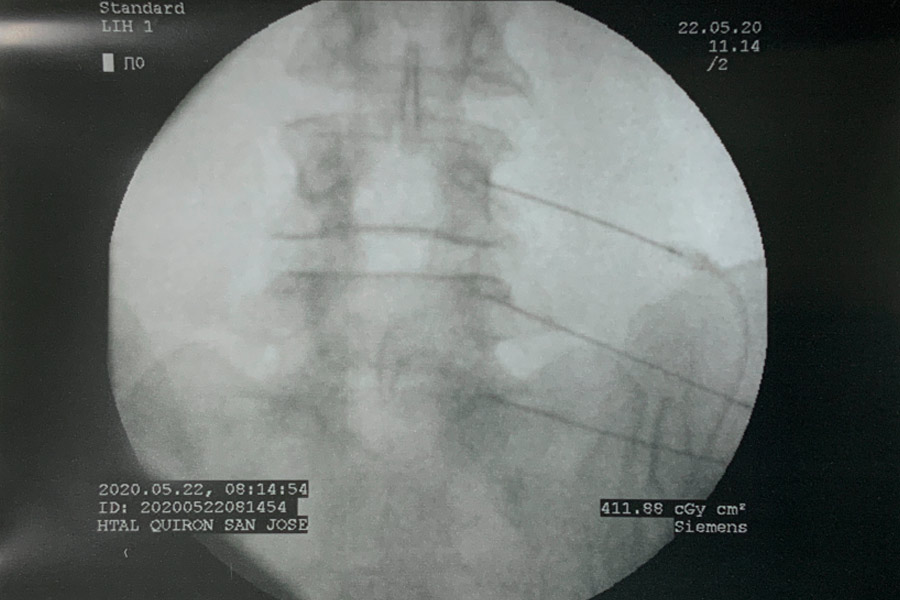

Caso clínico: endoscopia de columna multinivel L4L5 y L5S1

Durante la intervención quirúrgica, se abordarán los dos niveles mediante la técnica de endoscopia de columna.